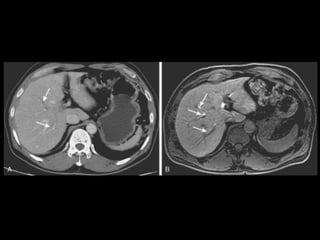

• TC: Tres fases

– Arterial (10 a 20 segundos)

– Fase venosa portal ( 30 segundos )

– Fase venosa hepática (60 segundos)

• TC Portografia: Metastases.

Técnicas de Imagem •US: Primeiro exame pedido ao: 1) dor no hipocondrio direito; 2) testes de função hepáticas anormais; 3) suspeita de malignidade. • TC: Tres fases – Arterial (10 a 20 segundos) – Fase venosa portal ( 30 segundos ) – Fase venosa hepática (60 segundos) • TC Portografia: Metastases.